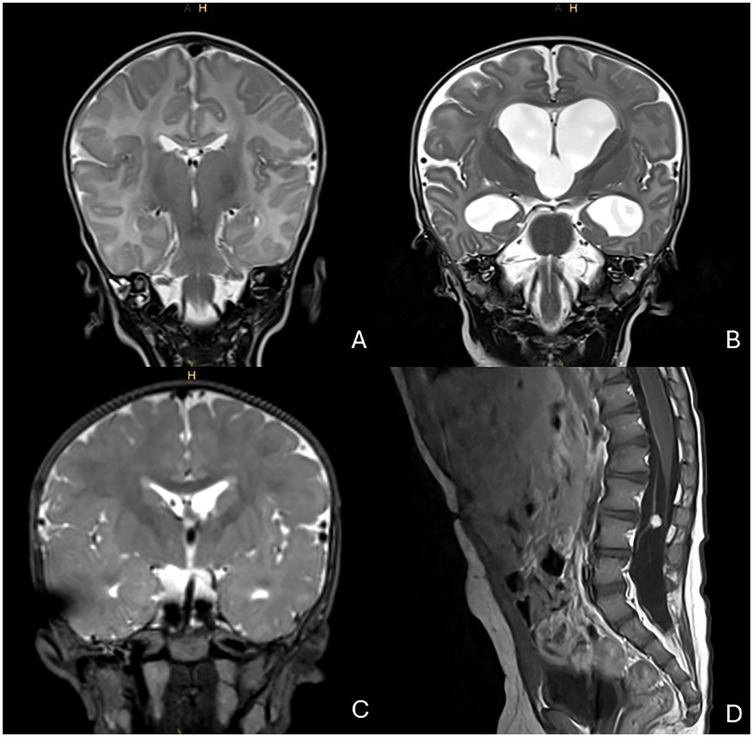

Pathogenic variants in the PIK3CA gene, which encodes the p110-α catalytic subunit of the phosphoinositide 3-kinase (PI3K), are commonly associated with overgrowth syndromes and cancer. We report a patient with the point variant c.1030G>A p.(Val344Met) in the PIK3CA gene who presented shortly after birth with viral sepsis and and severe lymphopenia, followed by colonic perforations. Histopathology showed ulcerative necrotizing colitis with lymphatic vascular malformation. The patient subsequently developed hydrocephalus requiring a ventriculoperitoneal shunt, complicated by refractory ascites that resolved with acetazolamide therapy. Awareness of the potential disease spectrum through early molecular diagnosis, combined with a comprehensive immunologic evaluation, enabled individualized management via closer clinical monitoring and timely interventions to prevent and control neurological and infectious complications. This case highlights the phenotypic heterogeneity of PIK3CA pathogenic variants and the importance of early precision medicine in pediatric care.